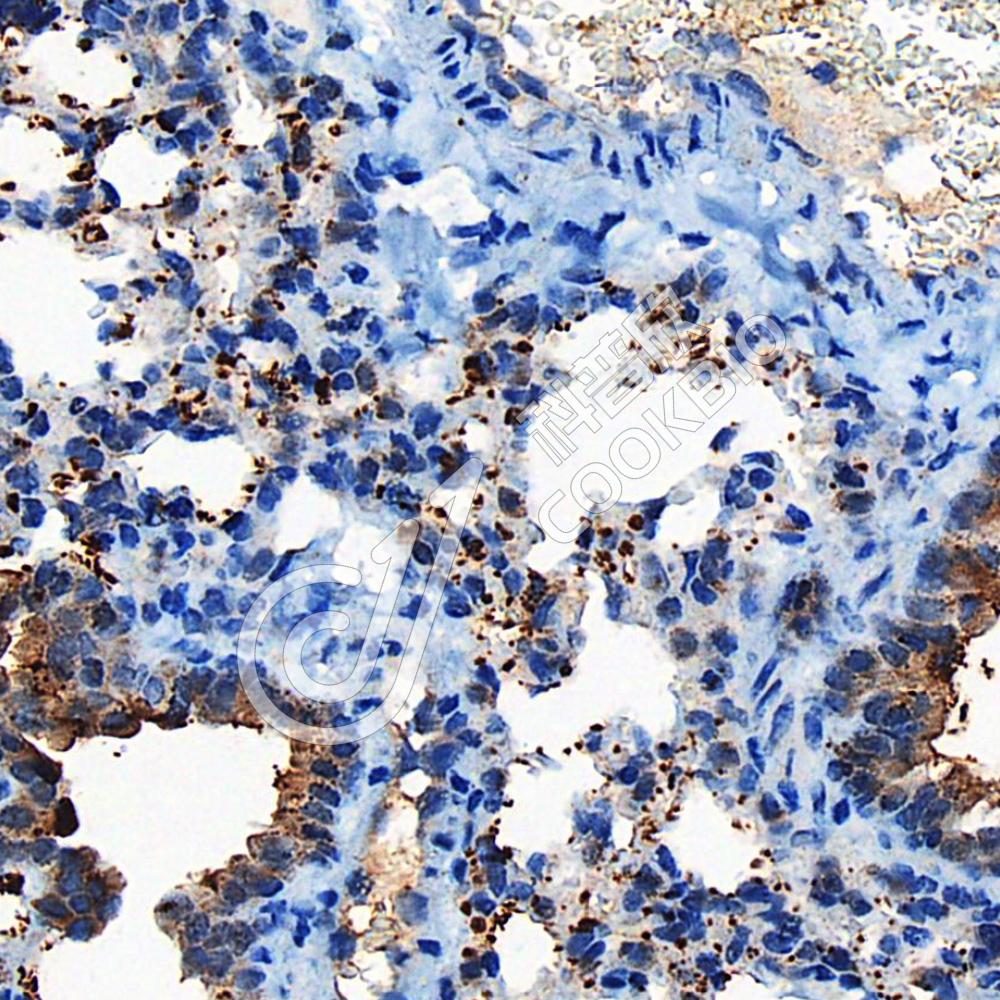

IHC检测Galectin 10蛋白(货号 K1344250).

样品: 人扁桃体, 4%多聚甲醛 (货号KSG1101) 固定12-24小时.

抗原修复: 柠檬酸抗原修复液(干粉, pH 6.0) (KSG1201), 98℃, 20分钟.

—抗: 1: 1400稀释, 4℃ 孵育过夜.

二抗: S-vision免疫组化多聚二抗(山羊抗兔),即用型 (货号KB3906), 室温孵育20分钟.

样品: 小鼠哮喘肺, 4%多聚甲醛 (货号KSG1101) 固定12-24小时.